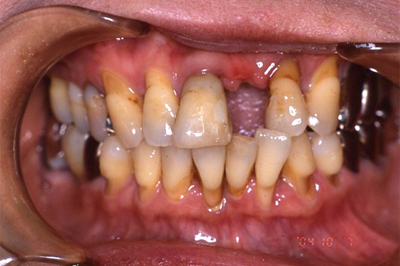

インプラント施術例

歯を削りたくない、入れ歯をどうしても入れたくないという時、インプラント治療を行っています。

施術前

施術後